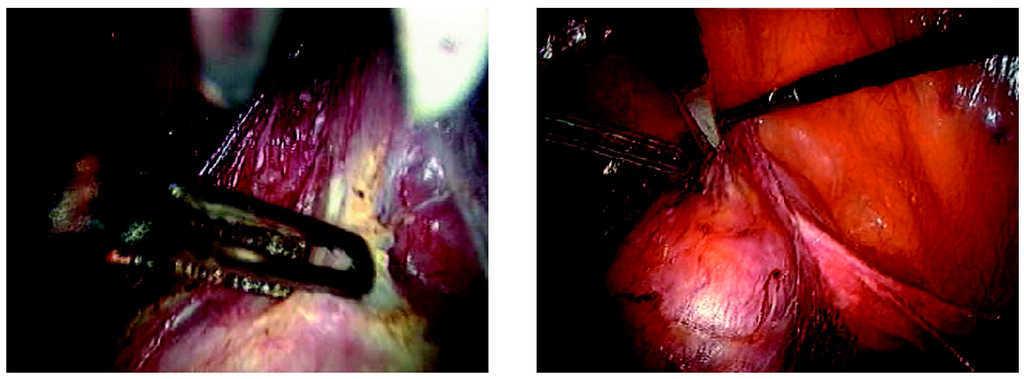

-- Paso primero. Disección del saco herniario de la cúpula vaginal y apertura de ésta (fig. 1).

Figura 1.Detalle del saco herniario de la cúpula vaginal.

-- Paso segundo. Resección del saco herniario y enterocele (fig. 2).

Figura 2.Detalle de la resección del saco herniario.

-- Paso tercero. Fijación de la malla de polipropileno a la cúpula vaginal con puntos de sutura no reabsorbible e introducción en cavidad abdominal de la malla y cierre de la cúpula con puntos de sutura aplicados por vía vaginal (fig. 3).

Figura 3.Detalle de la fijación de la malla a la vagina.